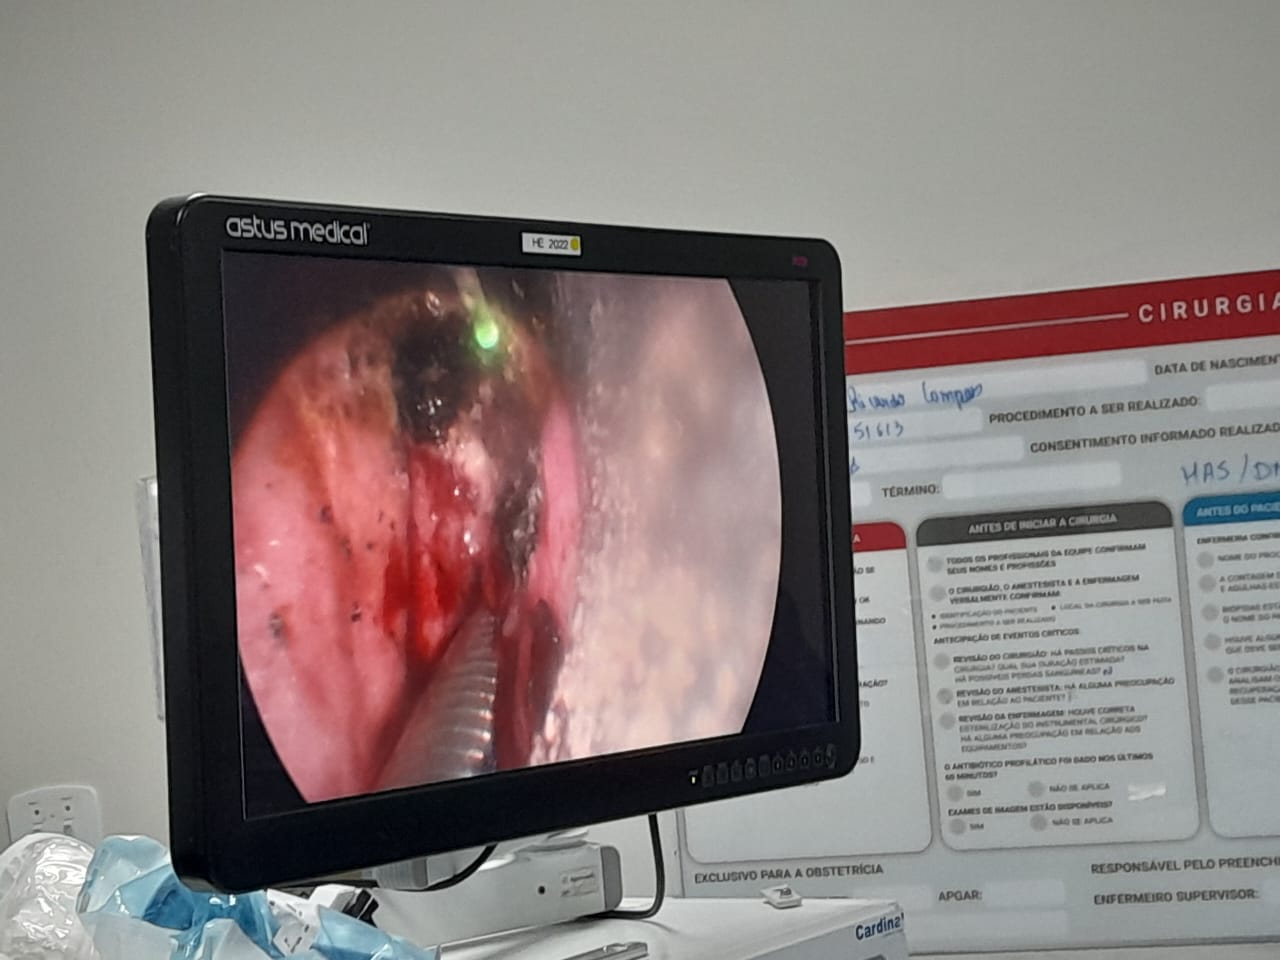

Um procedimento cirúrgico inédito no interior do estado do Rio de Janeiro foi realizado com sucesso no Hospital Dr. Beda, em Campos dos Goytacazes. A cirurgia tratou um câncer de laringe em um paciente de 77 anos, utilizando uma técnica a laser inovadora, denominada TOFLS (Cirurgia a Laser Flexível Transoral), com o uso do chamado Blue Laser. A responsável pelo procedimento foi a médica cirurgiã de cabeça e pescoço Thais Valente, que contou com o auxílio do também cirurgião Raphael Sepulcri.

Segundo Thais Valente, a cirurgia foi bem-sucedida e o paciente teve alta hospitalar já no dia seguinte ao procedimento, com recuperação tranquila. A técnica empregada, até então inédita no interior fluminense, permite o tratamento de tumores com mínima agressão aos tecidos adjacentes, dispensando a necessidade de traqueostomia em muitos casos. “Essa tecnologia emite um laser azul com ação fotoangiolítica e cortante, diferente dos lasers tradicionais como o de CO₂. Traz mais precisão e menos riscos ao paciente”, explicou a médica.

A cirurgia durou cerca de duas horas e consistiu numa cordectomia tipo IV, com retirada da corda vocal e da camada muscular adjacente. O paciente, tabagista de longa data, já havia feito radioterapia para o mesmo câncer. “A escolha do laser foi estratégica para minimizar os riscos e acelerar a recuperação. Ele se alimentou normalmente logo após o procedimento e agora deverá fazer fonoterapia e acompanhamento médico regular para monitorar possíveis recidivas”, informou a cirurgiã.